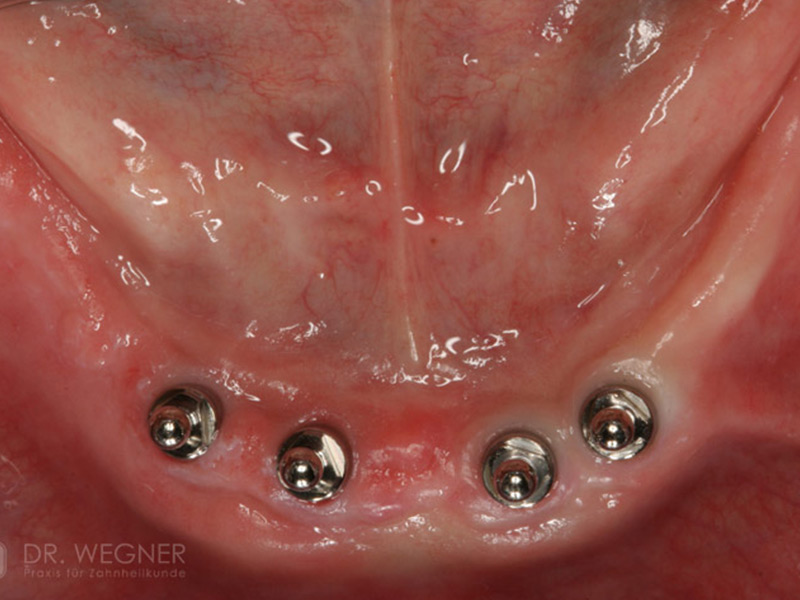

Zahnimplantate werden anhand von moderner virtueller 3D-Planung passgenau geplant und inseriert. Der Vorteil von Implantaten besteht darin, dass festsitzender ästhetischer Zahnersatz auch in solchen Fällen realisiert werden kann, in denen sonst nur herausnehmbare Prothesen möglich wären. Zudem ist im Gegensatz zur Brückenprothetik kein Beschleifen der Nachbarzähne notwendig.

Unter dentalen Implantaten versteht man im allgemeinen eine Schraube, die dort, wo ein oder mehrere Zähne verloren gegangen sind, in den Kieferknochen "eingepflanzt" wird. Diese Therapieform der Implantologie hat sich in den letzten Jahren zu einem alltäglichen Therapieverfahren in der Zahnheilkunde entwickelt. Wissenschaftliche Untersuchungen zeigen hierfür eine Erfolgsquote von i. d. R. 80-98 % über 10 Jahre. Verglichen mit anderen zahnärztlichen Maßnahmen gibt es nahezu keine andere Therapie mit derart guten Erfolgsaussichten. Auch eine Verbesserung der Lebensqualität wird durch implantatgetragenen Zahnersatz laut klinischer Studien erreicht.

Mittlerweile hat sich die Implantologie zu einem alltäglichen Therapieverfahren mit sehr guten Erfolgsaussichten in der Zahnheilkunde entwickelt. Bei guter Mundhygiene und regelmäßigen Kontrolluntersuchungen können fachmännisch gesetzte Zahnimplantate ein Leben lang halten.